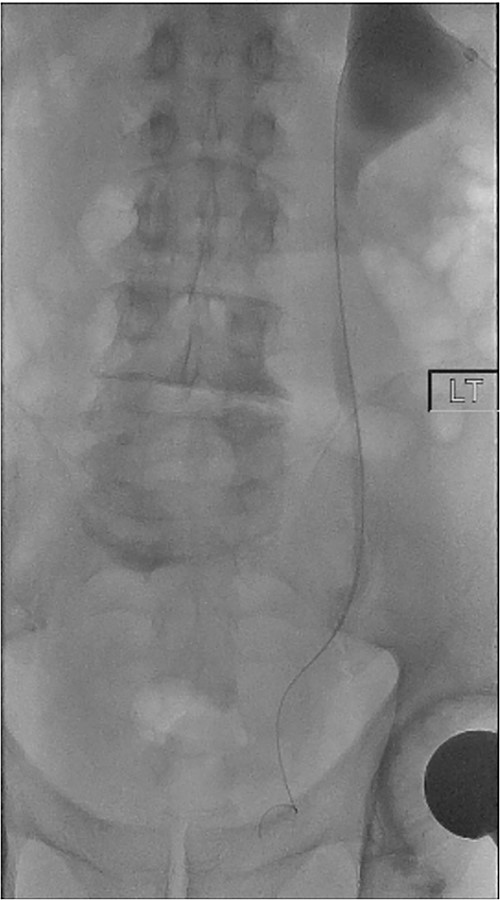

On Day 5 post-operatively, bilateral nephrostograms revealed bilateral ureteric occlusion at the level of the VUJ with extravasation at the right side (Fig. 1). An attempted antegrade ureteric stent insertion failed. The patient was thereafter booked electively for a rigid cystoscopy and bilateral ureteric stenting 3 weeks following the original operation.

On both cases, under general or regional anaesthesia, a cystoscopy was performed and the interureteric bar was identified. A hybrid ‘sensor’ or ‘Terumo’ hydrophilic guidewire was advanced concurrently using the access from the existing nephrostomy tube with fluoroscopic assistance down to the level of the ureteric cul-de-sac. A combined visual- and x-ray-guided approach verified the exact location of the course of the intramural ureter, in correlation to the resectoscope and a Collins knife was used to incise the bladder mucosa (Fig. 2) above the level of the guidewire, on the virtual course of the intramural ureter exposing the intramural ureter. In all three attempts, the incision of bladder mucosa above the antegrade ureteric guidewire ended up with a successful identification of the guidewire, allowing access to the ureteric cul-de-sac. Stent graspers were used to snare the guidewire into the bladder (Fig. 3). With safety wire in place, management of the neo-orifice could then be performed.

A combined visual- and x-ray-guided approach verified the exact location of the course of the intravesical intramural right ureter, in correlation to the resectoscope. (A) X-ray, (B) cystoscopic view.